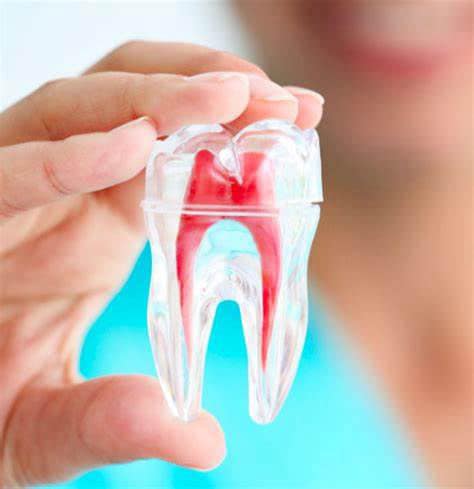

What is |Root Canal Treatment

Root canal treatment, also known as endodontic therapy, is a dental procedure aimed at treating infection or damage within the tooth’s pulp, the soft tissue inside the tooth that contains nerves, blood vessels, and connective tissue. This treatment is designed to save a tooth that might otherwise need to be extracted.

Steps Involved in|Dental Root Canal Treatment

A small opening is made in the crown of the tooth to access the pulp chamber.

The infected or damaged pulp is removed using specialized instruments. The root canals are then cleaned and shaped to ensure they are free of bacteria and debris.